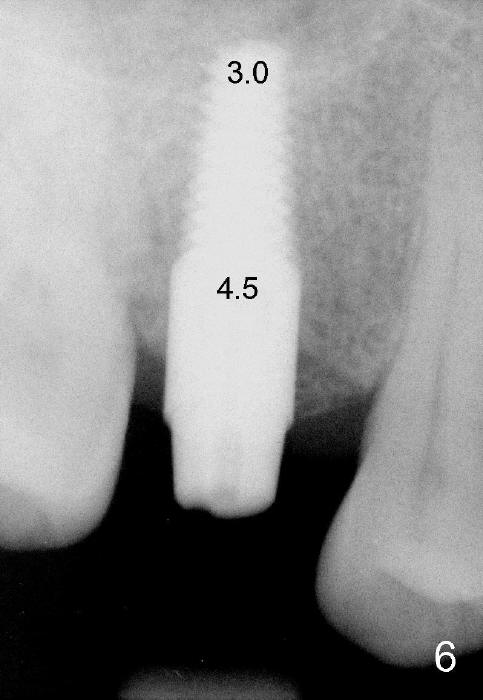

The 42-year-old lady is a dental phobic. The tooth #3 (residual root) is extracted 3.5 years ago. Finally she returns for implant (Fig.1). The mesiodistal space allows to place a 5x14 mm implant (Fig.2). Bone density is felt low when a 1.6 mm pilot drill is used. Bone condensation proceeds with bone expanders 2.6 mm (Fig.3) to 3.8 mm (Fig.4) 12 mm deep. Bone density is felt to increase with each larger expanders. When a 4x11 mm implant is placed (Fig.5), the insertion torque is 15 Ncm. When the diameter and length of the implant increase (Fig.6), the insertion torque is >60 Ncm. To have primary stability, the implant should be two sizes larger than the last expander (compare Fig.4,6)! In addition, the majority portion of the expanders is cylindrical (Fig.3,4), whereas the implant is tapered (Fig.5,6).